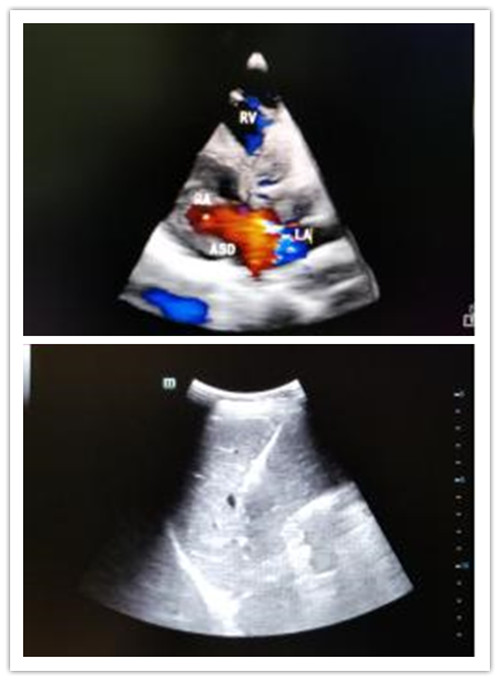

(三)心血管腔疾病超声诊断

包括常规超声心动图检查、颈部动静脉、腹腔动静脉、肾动脉、四肢大动脉及深静脉系的形态结构、血流动力学检查。超声心动图检查系将超声探头置于胸壁、食管内,对立体的心脏进行无数切面扫描、综合分析心脏各结构的位置、形态、活动与血流特点,从而获得心血管疾病的解剖、生理、病理及血流动力学诊断资料。近年来食管内超声、血管内超声、心血管三维超声成像技术的发展,进一步拓宽其应用范围,大大提高了诊断敏感性与特异性。

1、先天性心血管结构异常。如房缺、室缺、法乐氏三、四联症、动脉导管未闭、心内膜垫缺损、大动脉转位、肺静脉畸形引流、先天性瓣叶发育畸形等。

国内第一台心脏四维彩超PHILIPS-EPIC-7C

心脏四维